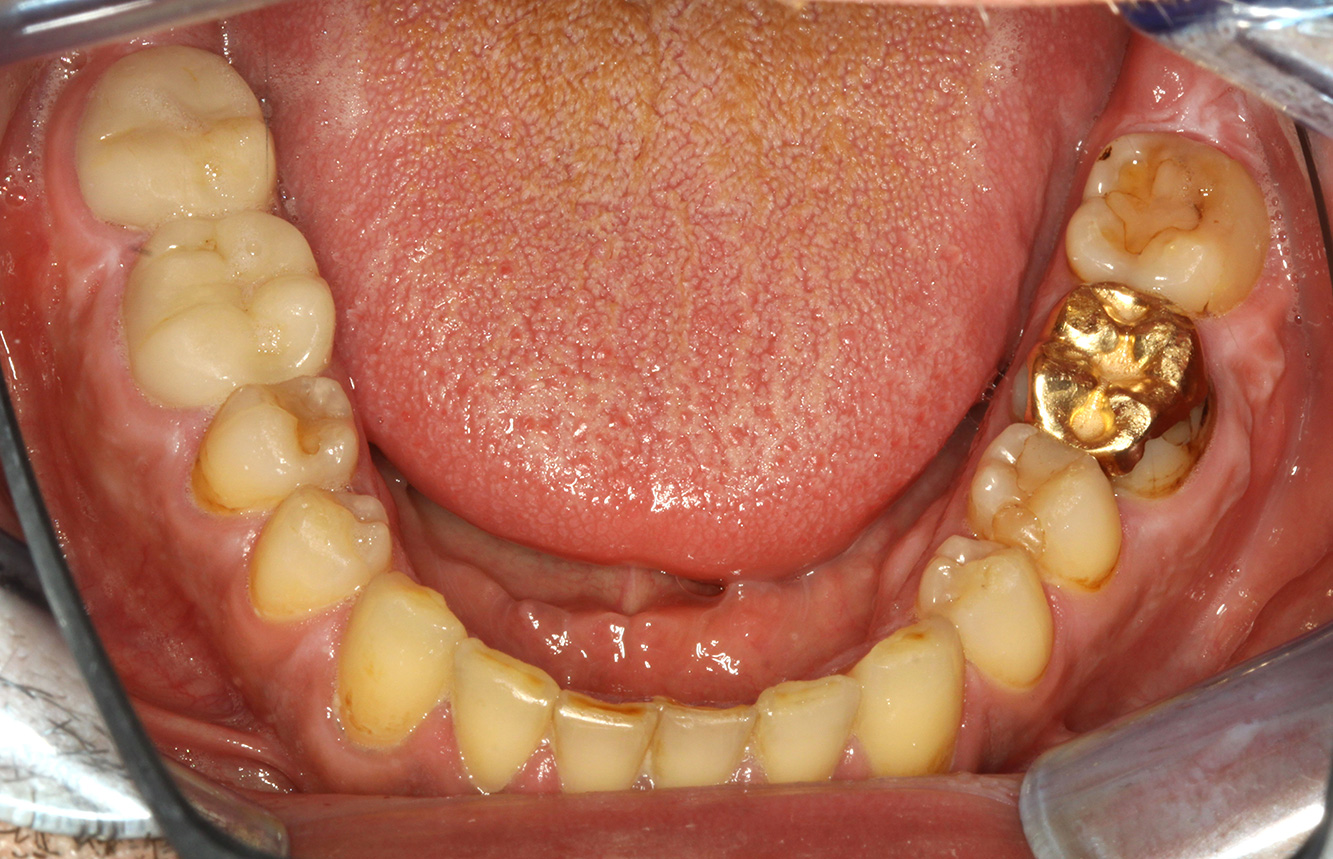

The healthy patient with pre-existing periodontal disease & peri-implantitis